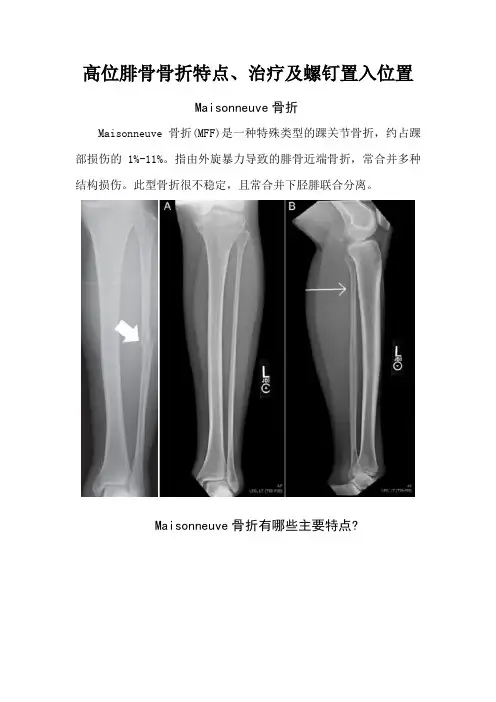

高位腓骨骨折特点、治疗及螺钉置入位置Maisonneuve骨折Maisonneuve骨折(MFF)是一种特殊类型的踝关节骨折,约占踝部损伤的1%-11%。

指由外旋暴力导致的腓骨近端骨折,常合并多种结构损伤。

此型骨折很不稳定,且常合并下胫腓联合分离。

Maisonneuve骨折有哪些主要特点?1. 骨间膜损伤及腓骨近端骨折;2. 踝关节内侧结构损伤(内踝骨折或三角韧带损伤);如果踝关节内侧结构损伤是三角韧带断裂,同时下胫腓全部韧带损伤,而从X线片上仅可见到腓骨中上1/3骨折,甚或腓骨颈骨折或上胫腓分离,此时不应忽略踝关节损伤与下胫腓分离存在的重要性,我们在临床中应高度重视此情况的发生。

3. 下胫腓前韧带损伤;4. 可合并下胫腓后韧带损伤或后踝骨折。